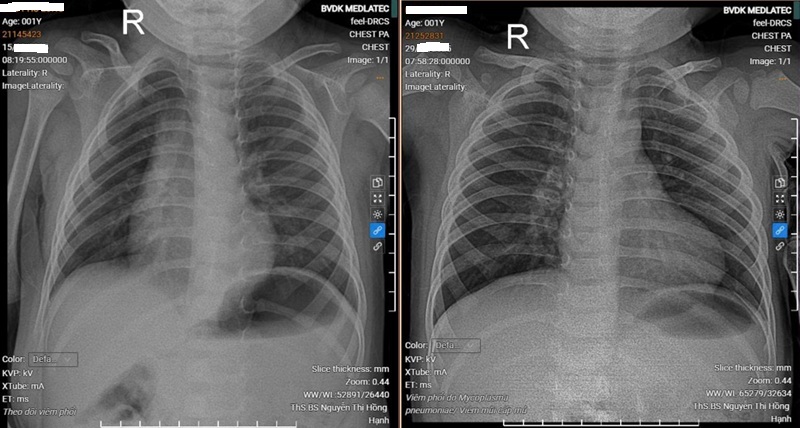

- X-quang phổi: Hình ảnh viêm phổi mô kẽ lan tỏa hai bên, nổi bật vùng phổi phải, tổn thương dạng mờ lưới – nốt mịn, không đông đặc, đặc trưng cho viêm phổi do Mycoplasma pneumoniae.

Kết quả chụp X-quang phổi của bệnh nhân trước và sau khi điều trị

Từ các kết quả trên, bác sĩ chẩn đoán trẻ mắc viêm phế quản phổi do Mycoplasma pneumoniae kèm theo viêm mũi cấp mủ. Trẻ được chỉ định điều trị ngoại trú bằng kháng sinh đặc hiệu, kết hợp vệ sinh mũi họng và theo dõi tái khám định kỳ. Sau một thời gian điều trị, trẻ giảm ho rõ rệt, hết khò khè, dịch mũi ít và sức khỏe ổn định.